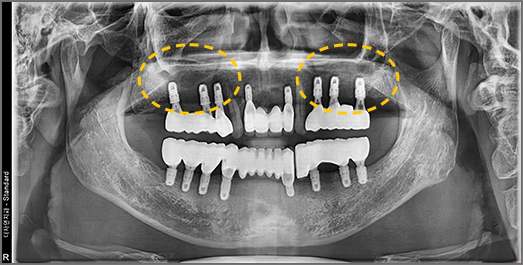

Sinus Lift (Sinus Augmentation)

We build up the bone where needed, even when alveolar bone is insufficient.

The maxillary sinus is an air-filled cavity located on either side of the nose, just above the upper alveolar bone, and is lined by a thin membrane. When placing implants in the upper posterior molar region, insufficient alveolar bone in this area may cause the implant to penetrate into the sinus cavity. To prevent this, a surgical procedure called sinus lift (sinus augmentation) is performed — which involves elevating the thin sinus membrane and grafting bone material into the space beneath it.

• BEFORE: 2021.02.01

• AFTER: 2021.05.13